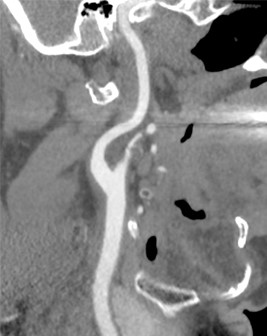

На сегодняшний день это одна из наиболее распространенных методики оценки состояния внутренних органов посредством лучевой диагностики. Процедура заключается во введении контрастного вещества в локтевую вену через автоматический шприц. Благодаря МСКТ-ангиографии всего за 5-10 мин. доктор сможет с высочайшей точностью определить наличие тех или иных заболеваний сосудистой системы – артериального расширения (аневризмы), стеноза (сужения), окклюзии (полной закупорки). Кроме того, обнаружит сосудистую опухоль, аномалию строения сосуда и так далее.

Минимальное количество времени, требуемого для проведения диагностики, существенно снижает лучевую нагрузку на больного. МСКТ-ангиография является информативной и точной методикой, позволяющей получить трехмерное изображение тканей и органов с высокой степенью разрешения.

Единственным недостатком метода является статичность, т.е. невозможно получить изображение в режиме реального времени. При этом нельзя увидеть процесс кровенаполнения сосуда и оценить, в каком направлении движется кровь

Сонные артерии на компьютерном томографе в режиме 3D-реконструкции

Здоровая сонная артерия на МСКТ

Пораженная сонная артерия на МСКТ